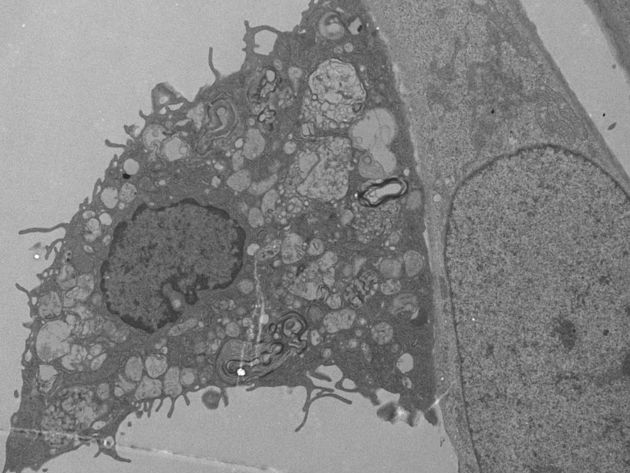

Figuur C - interactie vet-geladen macrofaag en glioblastoom

Figuur C

Een microscopie plaatje die de interactie laat zien tussen een vet-geladen macrofaag (links) en een glioblastoom cel (rechts).

Myeline is zichtbaar (de ronde gelaagde structuren) waarnaast vetdruppels zichtbaar zijn.